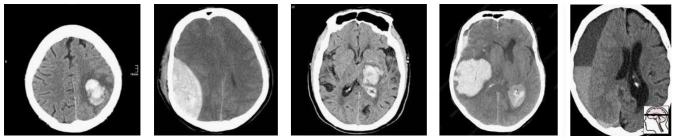

那么我们如何处理多重假设检验呢?一切都归结于问题的原因,那就是数据。Epi101 告诉我们,任何测试集都是目标群体的有偏版本。在这种情况下,目标人群是「所有 CT 头部成像的患者,有或没有颅内出血」。让我们来看看这种偏差是如何产生的,举一个假设人口很少的演示例子:

在这个人群中,我们有相当合理的「临床」病例组合。脑内出血 3 例(可能与高血压或中风有关),外伤性出血 2 例(右侧硬膜下出血,左侧硬膜外出血)。

现在,让我们对这个总体进行采样,以构建我们的测试集:

随机地,我们最终会有大部分额外的轴(大脑本身以外)出血。一个在这个测试中表现良好的模型不一定能在真实的病人身上发挥作用。事实上,你可能会期待一个模型,它真正擅长识别轴外出血。